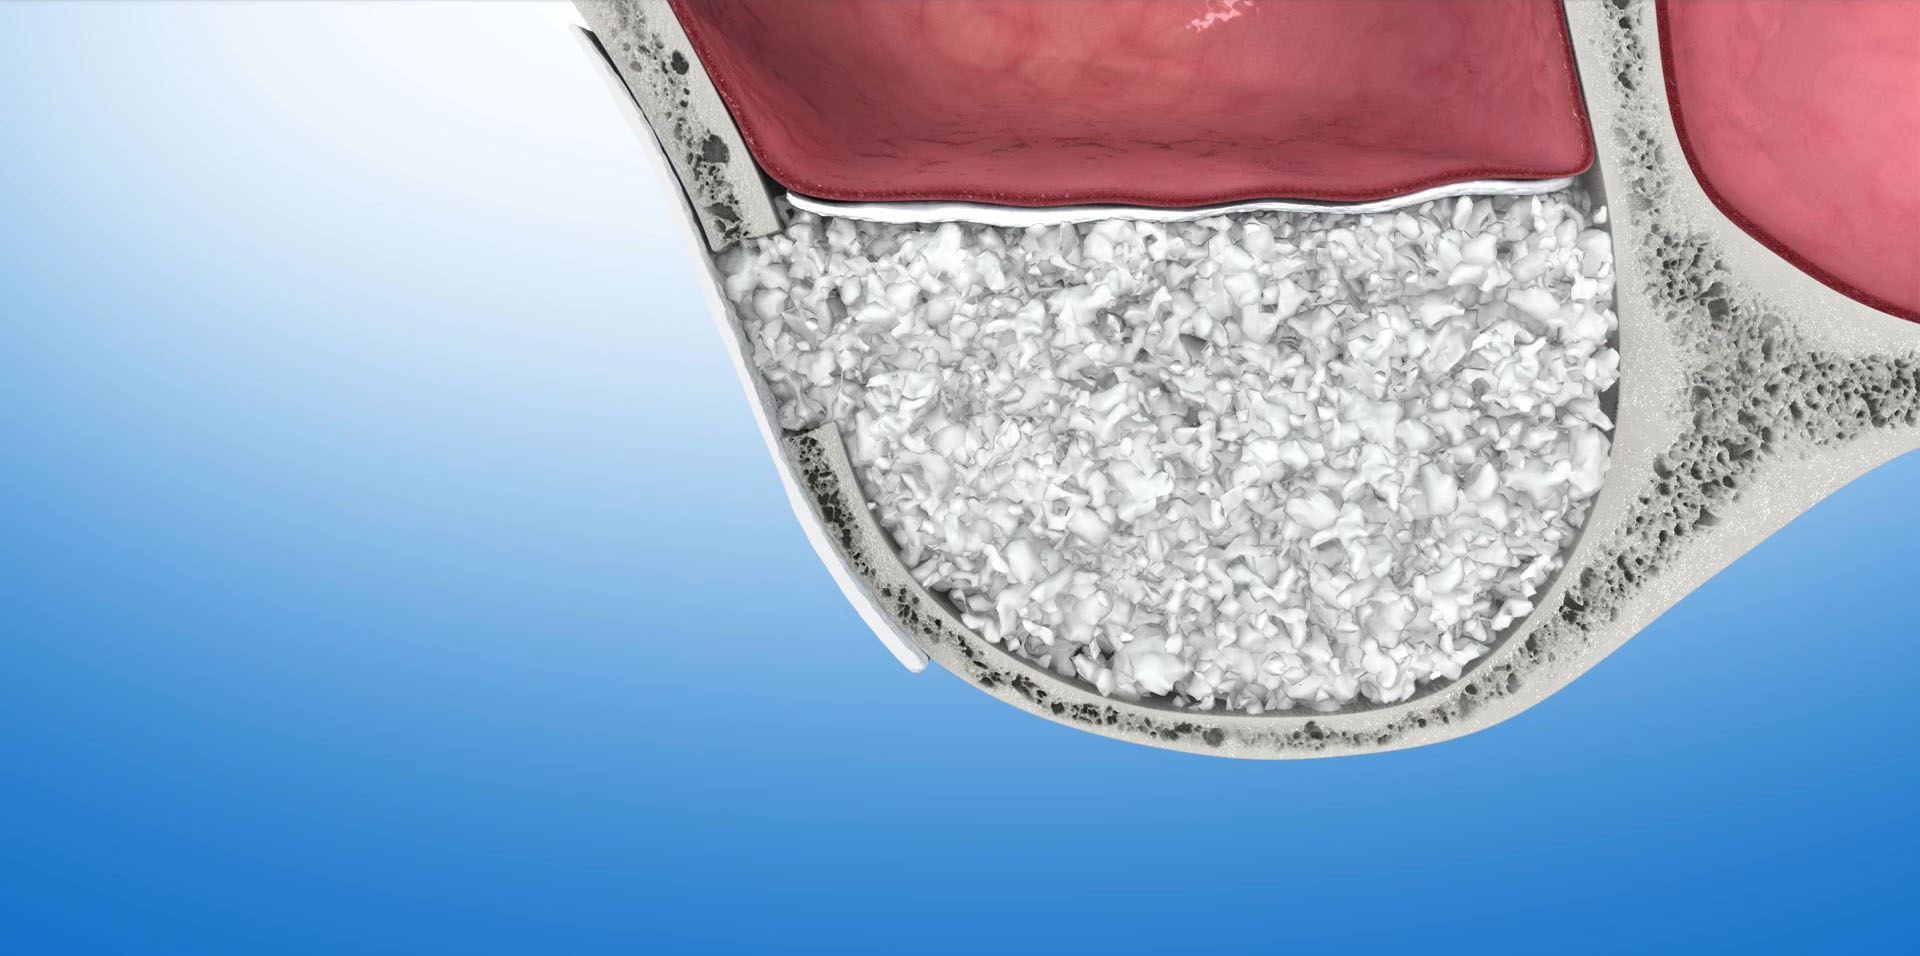

Do sterowanej regeneracji kości wykorzystywane są biomateriały – czyli substytuty kości oraz kość własną pacjenta. Często używane są równocześnie. Do pokrycia augumentatu czyli materiału odbudowującego kość używamy specjalnych membran, które stanowią barierę dla tkanek miękkich. Ogromna różnorodność na rynku biomateriałów pozwala na optymalny wybór w każdym konkretnym przypadku. W naszej Praktyce, zdecydowana większość zabiegów odbudowy kości przeprowadzana jest z zastosowaniem materiału kościozastępczego Bio-Oss oraz kolagenowych resorbowalnych membran Bio-Gide firmy Geistlich.

Bio-Oss

To materiał kościozastępczy produkowany z kości wołowych. W trakcie procesu produkcyjnego usuwane są z niego wszystkie składniki mogące powodować przenoszenie chorób lub wywoływać reakcje alergiczne. Naturalna struktura mineralna zostaje jednak nienaruszona. Wykazuje ona ogromne podobieństwo do struktury kości ludzkiej. Ten porowaty materiał o utkaniu ludzkiej kości stanowi doskonałe rusztowanie dla naczyń krwionośnych i komórek kościotwórczych. Stanowi matrycę, sieć dla tworzącej się tkanki kostnej. Z upływem czasu, ok.1mm w ciągu miesiąca, Bio-Oss ulega resorbcji, a miejsce po nim zajmuje nowo wytworzona kość.

Podniesienie dna zatoki szczękowej metodą otwartą

Polega na wycięciu w bocznej ścianie zatoki małego okienka, przez które narzędziami ultradźwiękowymi i ręcznymi delikatnie odwarstwiamy błonę śluzową zatoki od kości dna zatoki. W uzyskaną przestrzeń aplikujemy materiał kościotwórczy. Okienko pokrywamy membraną zaporowa i zamykamy dostęp do zatoki. Tą metodą możemy uzyskać nawet ponad 10mm nowej kości, która umożliwi nam implantację w tym obszarze. Po zabiegu następuje okres regeneracji kości, w czasie którego wprowadzony biomateriał zamienia się w tkankę kostną. W zależności od ilości użytego biomateriału i stopnia podniesienia dna zatoki okres ten może trwać od 6 do 12 miesięcy.